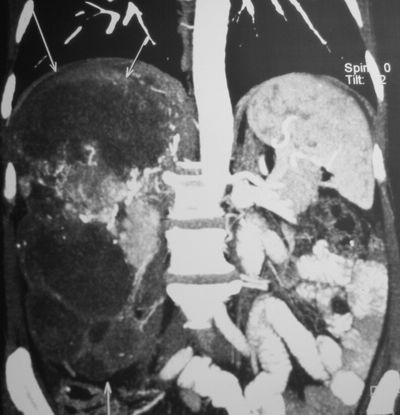

КТ органов брюшной полости.